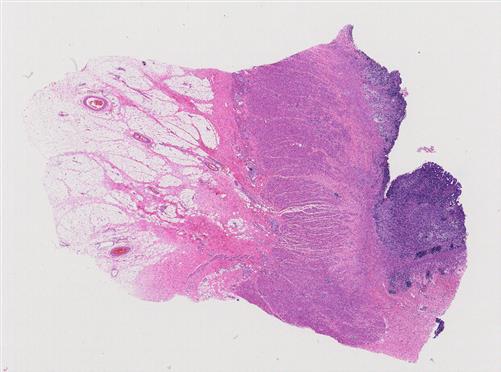

左腭 |

女, 30岁, 发现左腭肿物4年余,现逐渐长大,约2cm,带蒂,蒂不大,表面... |

常州市中医院 |